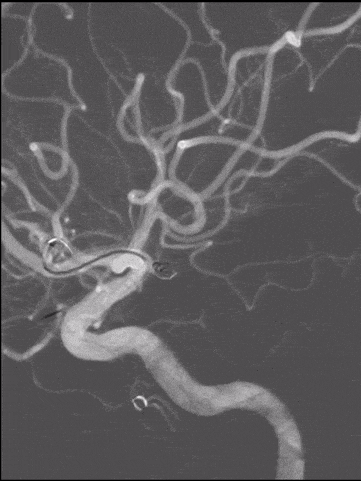

右侧颈内动脉造影

1.左侧大脑前动脉A1起始部未破裂动脉瘤(囊性)

2.右侧大脑前动脉A1起始部未破裂动脉瘤(夹层)